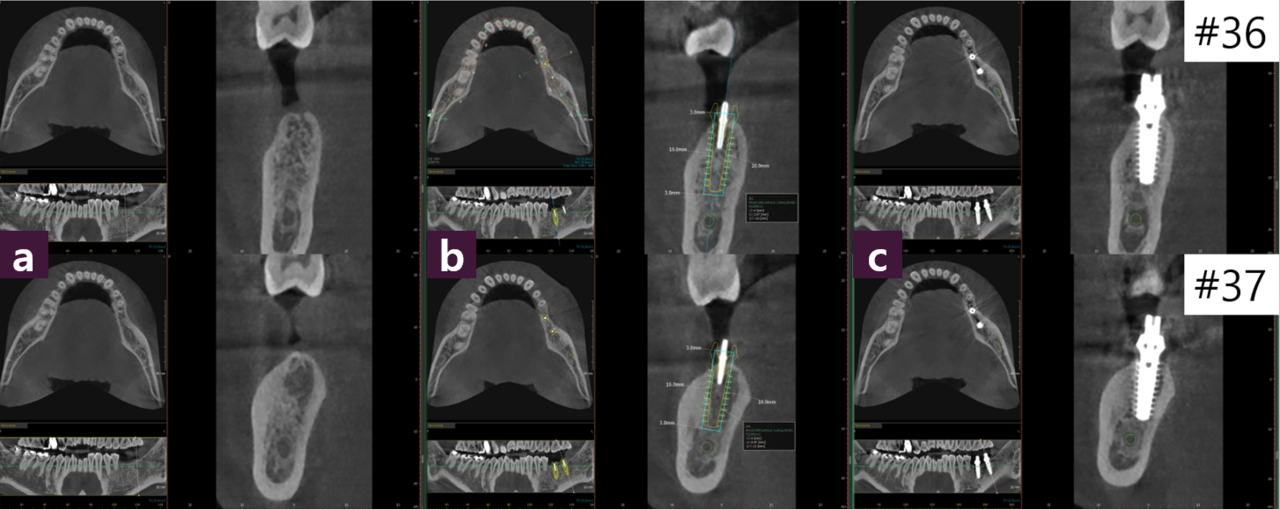

#36, 37 발치 후 2년여의 경과로, CT Axial view에서 #35 협설 치근단면 폭정도로 위축된 #36 치조제를 확인할 수 있다.

하지만, 추가적인 GBR 없이 Magic Fin Thread의 특성을 활용하여 좁은 골폭에서 최대 직경의 MagiCore를 식립할 수 있는 치료를 계획하고 한편, 부족한 부착치은은 최소 절개후 협측으로 확장하였다(그림3, 4).

이처럼 협설골폭이 위축된 경우에도 Magic GPS를 활용하는 식립 계획을 세울 수 있었고, 이를 통해 보다 정교한 임플란트 식립을 할 수 있었다.